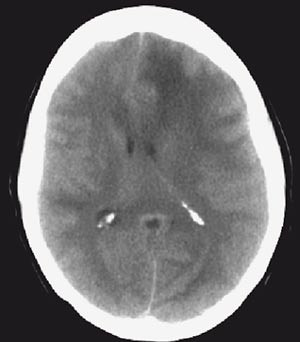

MR av hjernen viste utbredte signalforandringer i både grå og hvit substans i begge hemisfærer, mest uttalt på venstre side (fig 1). MR av ryggmargen var normal. Blodprøver viste SR 71, CRP 67 og LPK 12,1. Spinalvæske viste ingen leukocytter, protein 0,43 g/l og glukose 3,8 mmol/l. Samtidig serum-glukose var 4,9 mmol/l. EEG viste generaliserte funksjonsforstyrrelser med lett venstresidig overvekt. Røntgen thorax tatt tredje døgn etter innkomst viste bilaterale basale lungefortetninger.